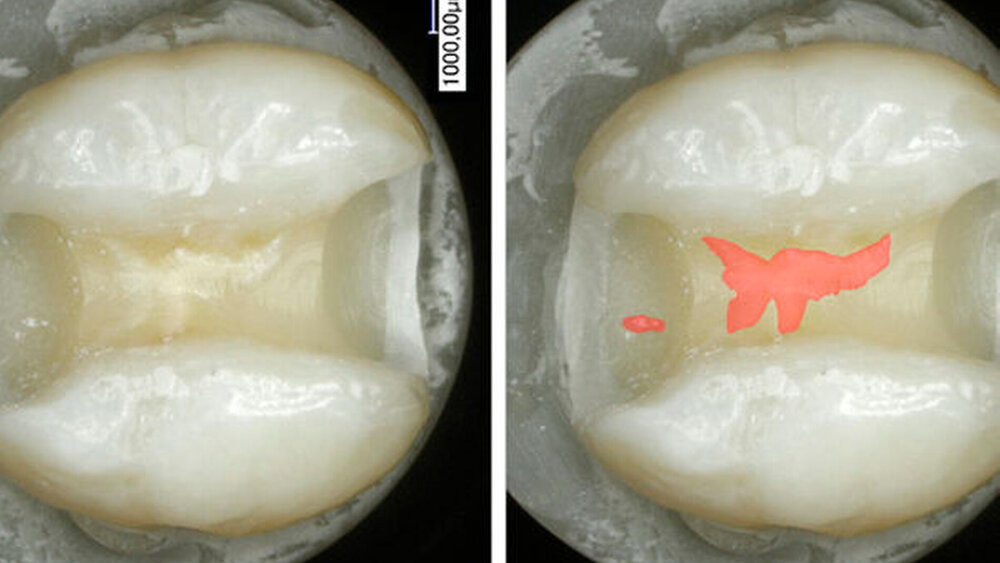

Sie präparierten in 50 karies- und füllungsfreie untere Molaren standardisiert Klasse-II-Kavitäten, wogen sie und bestimmten deren Volumen. Nach Konditionierung mit Phosphorsäure und Adhäsiv erhielten 25 Proben einen zahnfarbenen Liner und 25 ein weiß-opakes Flowable in einer ein Millimeter dicken Schicht. Zum Schluss erhielten die Zahnproben eine zahnfarbene Kompositfüllung. Nun wurden die Proben randomisiert einem Forscher übergeben, der die Kompositfüllung unter Wasserkühlung so gut als möglich entfernte. Eine zweite Person begutachtete im Anschluss, wie exakt er die Füllung entfernt hatte. Beide Forscher wussten nicht, bei welchen Zahnproben der weiß-opake und bei welchen der zahnfarbene Liner verwendet wurde. Die Wissenschaftler wogen die Zahnproben nun erneut und bestimmten wieder deren Volumen. Zusätzlich untersuchten sie den Kavitätenboden noch unter dem Mikroskop auf verbliebenes Komposit.

Der weiß-opake Liner führte zu weniger Zahnsubstanzverlust

Der Zahnhartsubstanzverlust war deutlich geringer, wenn ein weiß-opaker Liner verwendet wurde. In der Arbeitszeit für die Füllungsentfernung und der Anzahl von Pulpakammerperforationen zeigten sich keine signifikanten Unterschiede. Einschränkend muss dazu jedoch angemerkt werden, dass klinische Faktoren im Patientenmund wie schwierige Licht- und Sichtverhältnisse oder eingeschränkte Mundöffnung, die die Entfernungszeit einer Kompositfüllung verlängern können, in dieser In-vitro-Studie nicht berücksichtigt wurden.